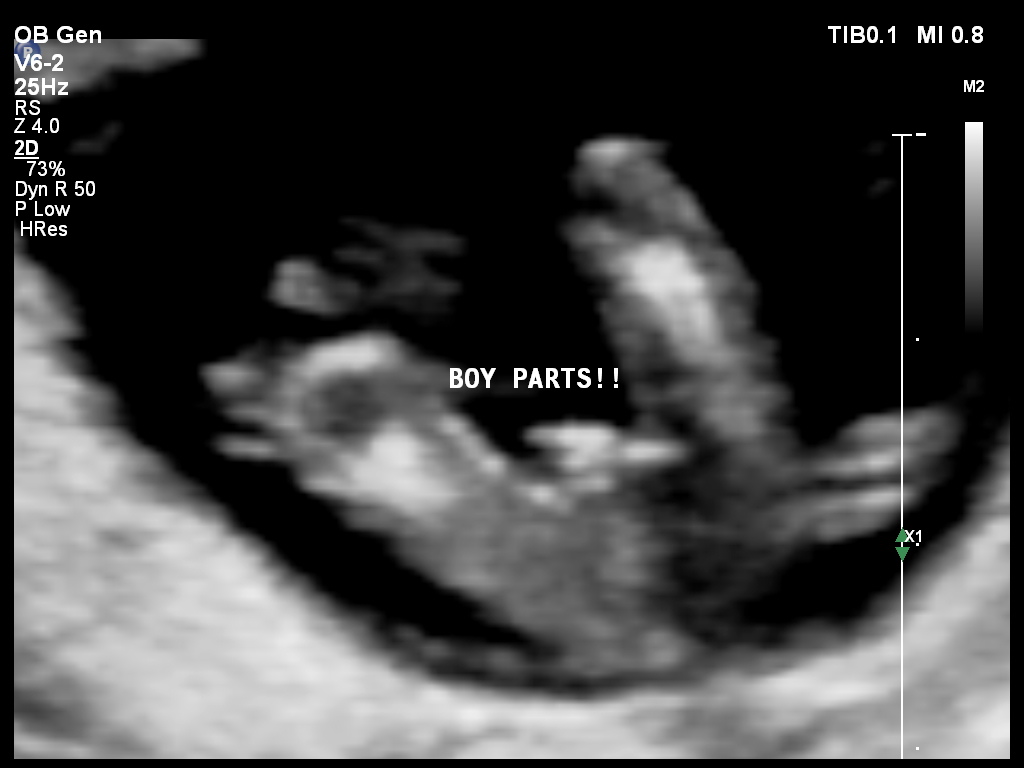

So excited to be posting here :-) We got 100% guaranteed confirmation (if that's even possible, but so she said, lol) that we are in fact having our boy!! Boy parts shown below!

Attachment 20631